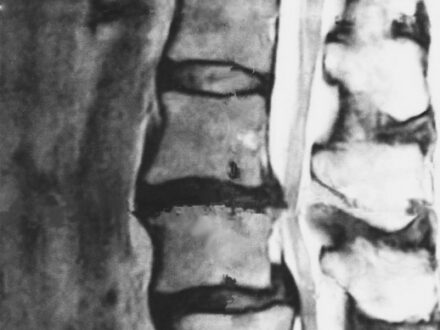

脊柱管狭窄症と黄色靭帯硬化症の……